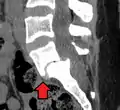

MRI of L5-S1 anterolisthesis

Anterolisthesis L5/S1